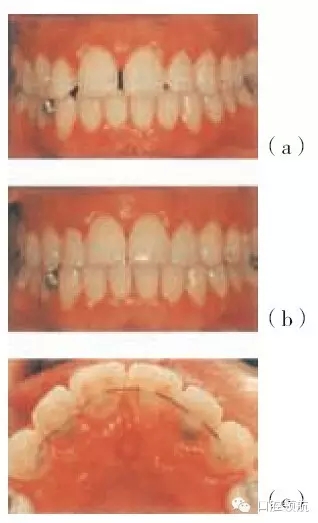

圖29.7 (a,b)圖29.4患者牙周治療之后的圖片,該患者不喜歡左下中切牙的位置及外觀,并希望盡可能保留該牙齒(有唇塌陷和局限性退縮)

圖29.8 圖29.7患者正畸治療的過程:(a)上頜固定矯治器。(b)上頜腭側(cè)保持器。(c)下頜固定矯治器。(d)排齊(永久保持)的上頜前牙及下頜固定矯治器。

左上中切牙經(jīng)正畸治療后更加美觀